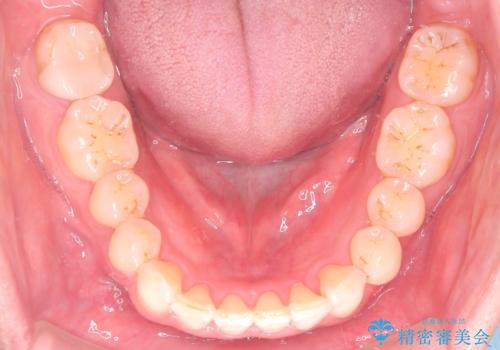

【インザライン】前歯の凸凹を治したい

- 前歯の凸凹を主訴に来院されました。

下顎位が右方に変異しており、外科矯正も提案しましたが患者様は希望されず、インビザラインにて治療を完了しております。

叢生のスペースを確保するために、臼歯部の遠心移動を行っています。

今回の治療計画は上顎の正中を顔と揃えることを優先しています。